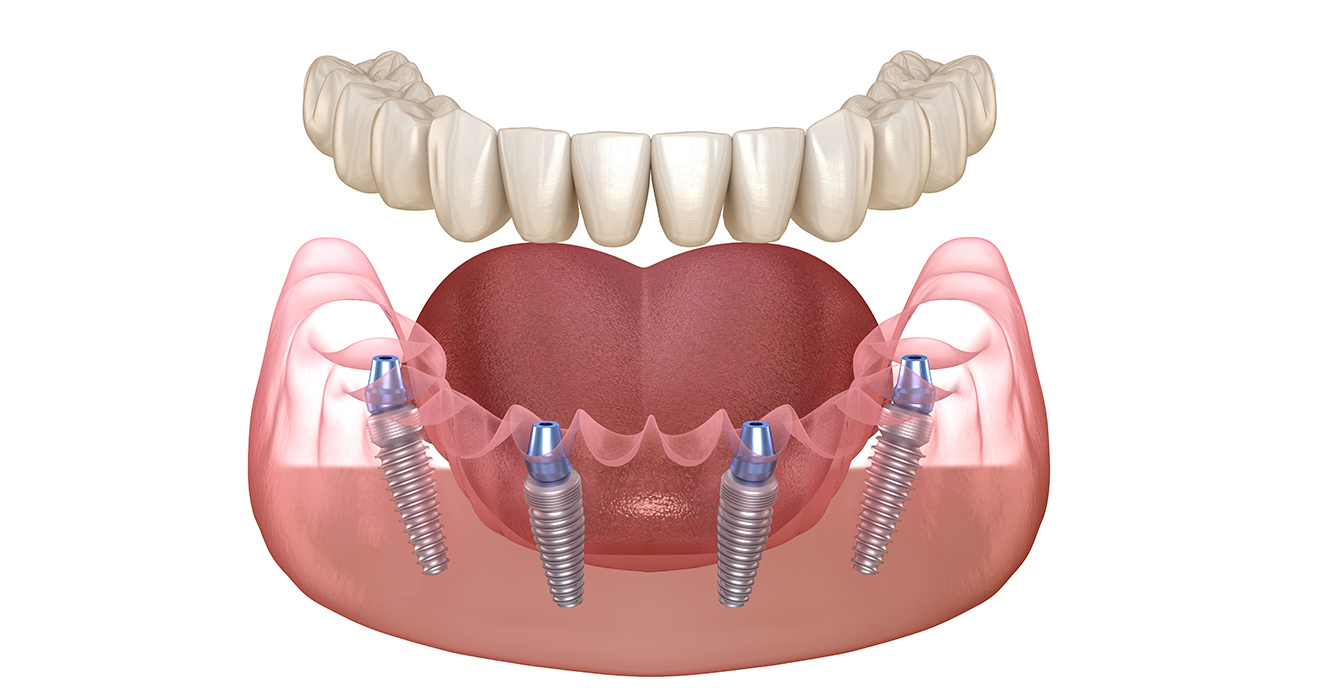

総入れ歯をお使いの方や、残存する天然歯の本数が少ない方向けの治療方法です。通常8本~14本のインプラントを埋入しなければいけないところ、オールオン4であれば4本~6本のインプラントで12本の歯を補うことが可能です。骨が減ってインプラント治療ができない方にもおすすめの治療法です。

医師の技術力によって術後の使用感が左右されるため、専門的な知識を持つ歯科医師が在籍する歯科医院を選ぶことが重要です。